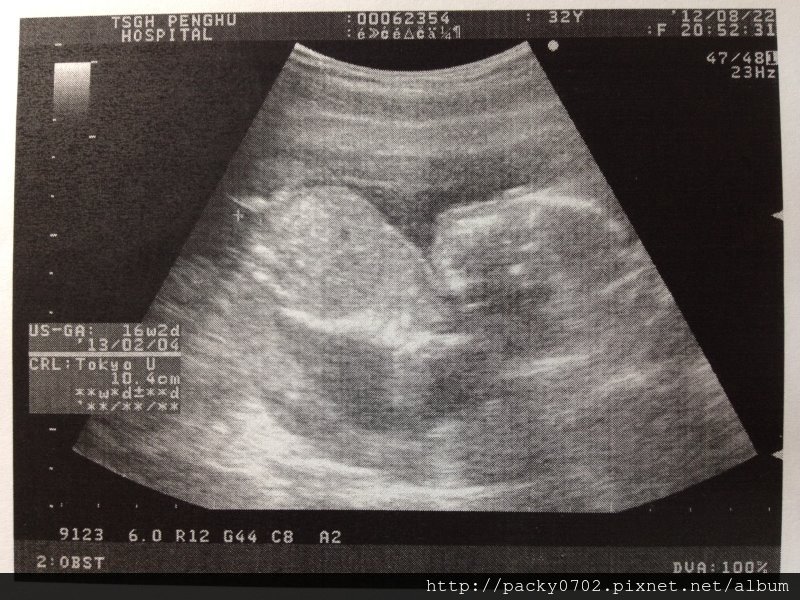

這時候小寶寶全長是10.4cm,但之後其實就不會量身長了~

20120822 (3)

這時候小寶寶頭圍是3.8cm,正常size

寶寶:身長10.4cm,頭圍3.8cm,肚圍13.0cm,大腿骨長2.6cm,重量225g